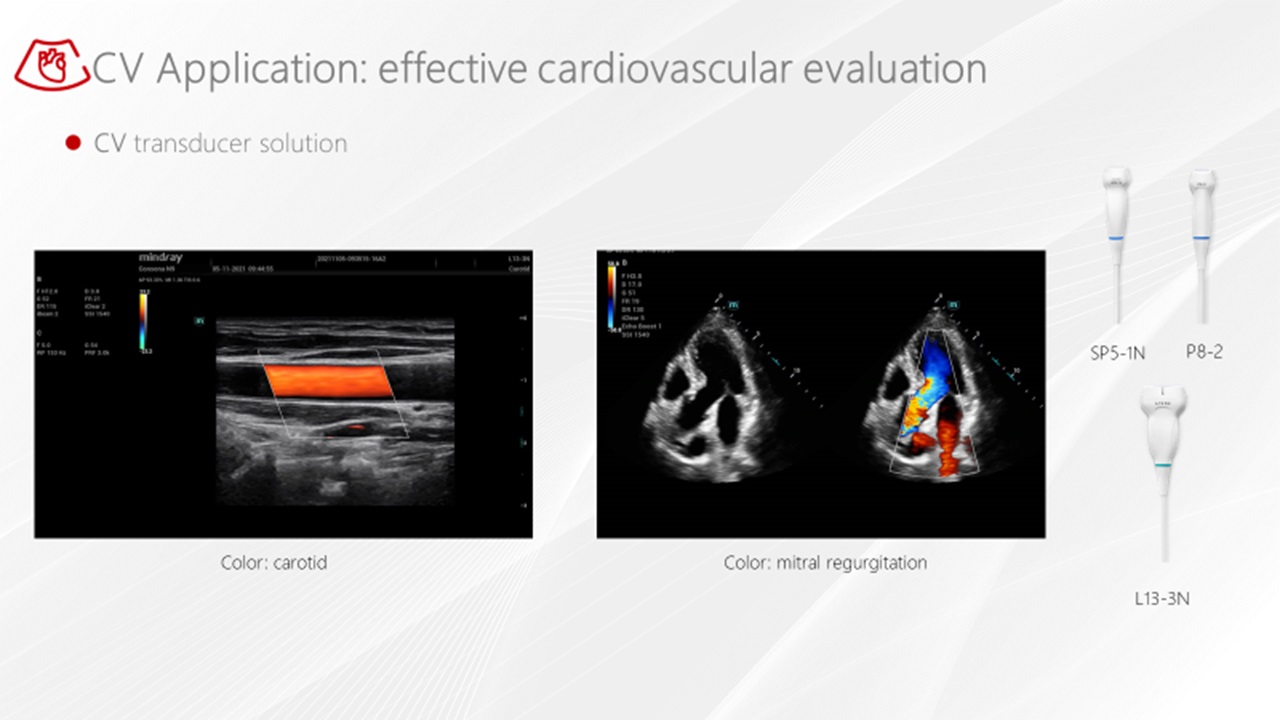

- RIMT - Rádiofrekvenčné meranie Intima Media

R-IMT

Rádiofrekvenčné hodnotenie a meranie IMT s vysokou presnosťou. RF-dáta merania IMT, obrazovo nezávislá automatická a mimoriadne presná IMT štatistika 6 kardiálnych tepov srdca v živom obraze.

R-VQS

Analýza tuhosti cievnej steny pomáha vo včasnej diagnostike a prevencií cievnych chorôb. Koeficient tuhosti ciev a pulznej vlny (PWV) sú vhodné na včasnú diagnostiku arteriálnej aterosklerózy.